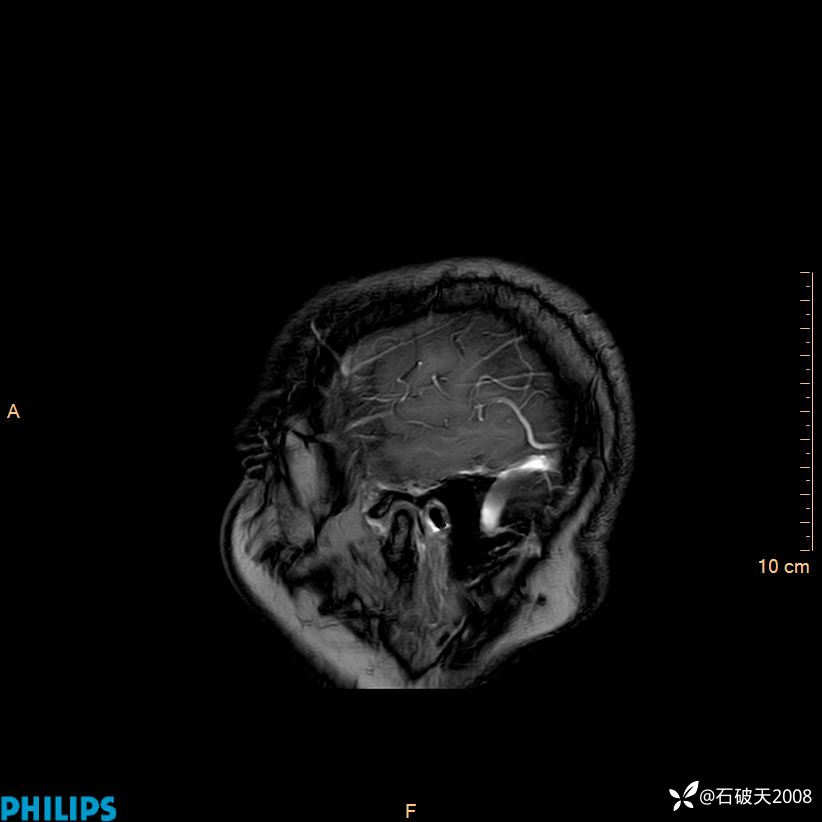

2024.2.21MR

增强矢状位